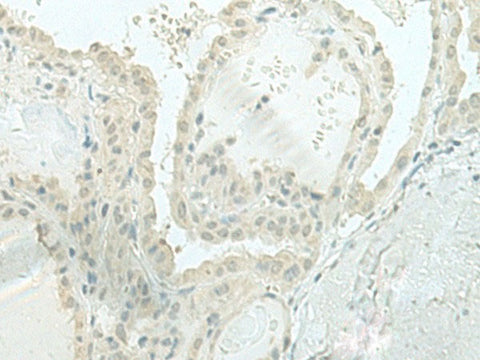

MIEN1 Polyclonal Antibody Reactivity Human

Reactivity Human, Mouse

Applications IHC

IHC 1:50-1:300